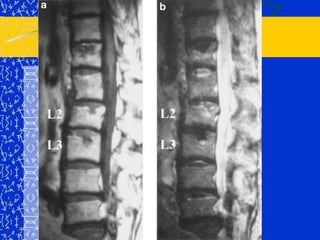

CIFOXIS CONGENITADebida a la falta de formación parcial o completa de la parte anterior de las vértebras y la falta de segmentación anterior de las vértebras adyacentes.Afectadas 1 – 3 vértebras, generalmente entre D10 y L2.

Cifosis Escoliosis